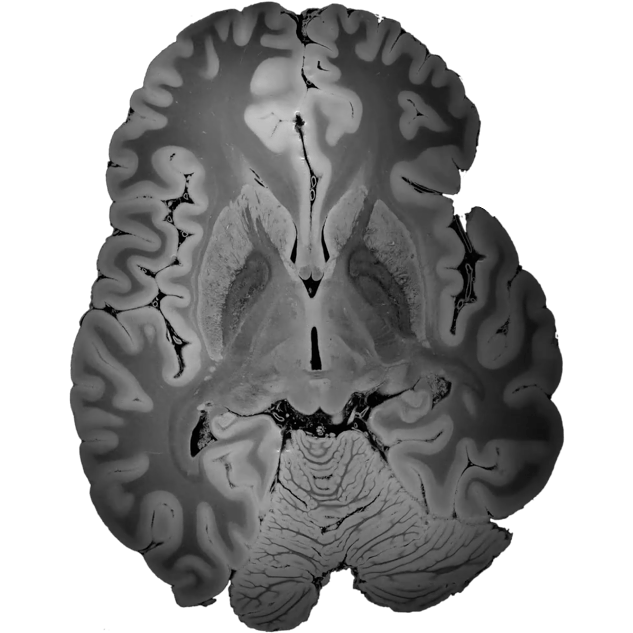

We offer artificial intelligence (AI) solutions for advanced assessment and analysis of brain MRI studies.

We develop innovative solutions based on artificial intelligence (AI) for advanced assessment and analysis of brain MRI studies. This is our response to the growing demand for effective tools supporting the diagnosis and monitoring of the course of neurodegenerative and demyelinating diseases.